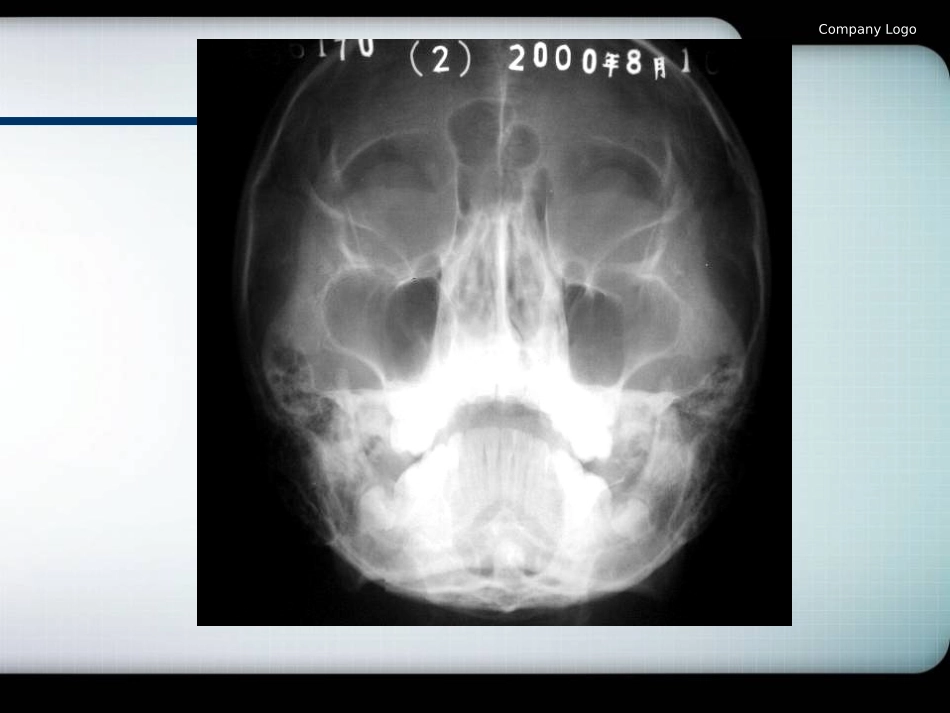

LOGO第八章、颌面骨骨折CompanyLogo常用片位1、华特位2、全景片3、颞颌关节位4、下颌开口后前位5、下颌升支侧位6、颧弓位7、鼻骨侧位CompanyLogoCompanyLogoCompanyLogoCompanyLogoCompanyLogoCompanyLogoCompanyLogoCompanyLogoCompanyLogo颌面骨骨折比较常见,约占全身所有骨折的3.2~3.8%。颌面骨外伤怀疑有牙及颌面骨骨折者均需要X线检查。X线检查的目的是确定骨及关节损伤的存在、部位、类型以及有无并发症。在治疗过程中可作为观察疗效的依据。第一节概第一节概论论CompanyLogo一、骨折的基本X线表现1、骨折线是贯穿密质骨与松质骨的透光线,呈线状或锯齿状,宽度不一,其形态多为横形、纵形、螺旋或丫形等。2、异常致密线骨折两端相重叠时可见,多见嵌入性骨折。3、骨小梁扭曲紊乱见于松质骨骨折。4、游离碎骨片多见于粉碎性骨折。5、压缩变形上颌骨颧骨骨折时可见上颌窦变形及积液。6、骨缝分离常见为骨缝裂开,如颧额缝等。CompanyLogo二、骨折X线片观察要点1、骨折的部位与数目2、骨折的类型3、骨折的移位4、骨折线与牙的关系5、骨折线与营养管及正常骨缝影像的区别CompanyLogo三、骨折的愈合(一)血肿形成期骨折同时有血管破裂出血,血肿充满断端组织间隙,骨折端附近骨细胞因损伤和缺血而死亡,血肿通常在伤后4~5小时即可凝固。(二)肉芽组织修复及机化期在折后24~48小时内,血肿周围有新的毛细血管和肉芽组织形成,以及成骨细胞开始长入血肿内,使血管机化。CompanyLogo(三)骨痂形成期骨折断端附近的骨外膜深层及骨内膜产生大量的成骨细胞,散布在两断端间的肉芽组织中,机化的血块逐渐变为骨样组织,再钙化形成骨痂。(四)成骨塑形期骨内外骨痂和桥梁骨痂完全融合并骨化,逐渐形成成熟骨结构,骨折线随骨痂的骨性愈合而消失,形成规律的骨板层和骨小梁。CompanyLogo[临床表现]有明显外伤史,颌面骨骨折有肿胀,疼痛、出血、畸形、功能障碍等表现CompanyLogo不同时期的骨折X线表现1、早期骨折线清晰,骨折断端有轻微的骨吸收,断端边缘不规则。2、中期骨折线逐渐模糊,密度增高,骨折断端有骨痂形成。3、晚期骨痂逐渐融合,塑形,骨折线消失,骨小梁排列逐渐规则。4、骨折愈合不良X线表现为骨痂出现延迟,稀少或不出现,骨折线消失迟缓或长期存在。5、骨折不愈合X线表现为骨折断端变圆、变宽、边缘光整,断端间有明显裂隙。CompanyLogo骨折愈合在X线片显示的时间取决以下因素:1、年龄2、营养3、健康状况4、骨折的性质及程度5、临床治疗情况X线片上一般在3~6个月可见骨性愈合征象,儿童时间要短些。而临床上在骨折1~2月后就基本愈合。CompanyLogo第二节、牙槽突骨折牙槽突骨折多发生在上颌前牙区.临床上牙槽突常伴有唇组织及牙龈损伤、肿胀、撕裂等,也可伴有牙脱位及牙折。牙槽突骨折以根尖片、颌片检查最清楚。X线上表现为横行、斜行及纵行骨折线条,应与营养管相鉴别。CompanyLogoCompanyLogo第三节、下颌骨骨折1、下颌骨位置较为突出,是颌面损伤的好发部位,约占颌面骨折的45%~79%。2、下颌骨骨折好发于下颌颏孔区、正中联合、体部、下颌角部及髁状突。3、下颌骨骨折除了受直接外力所致的骨折外,有时还有发生他处的间接骨折。4、下颌骨骨折后,骨折片的移位方向,除了外力作用的方向及大小外,最主要的是由于附着在骨面上的肌牵引。CompanyLogo[临床表现]局部软组织肿胀,疼痛,皮下出血形成大片瘀斑,有时可出现咀嚼及吞咽困难,咬合错乱,开口受限。骨折端移位后产生面部畸形,如有神经损伤则有下唇麻木。CompanyLogo[影像学表现]X线检查可选择下颌骨侧位、下颌骨后前位、下颌骨开口后前位、下颌前部颌片及全景片,髁状突骨折可选颞下颌关节侧位片,必要时可选用CT检查。下颌骨骨折可表现为单发、多发或粉碎性骨折,也可表现为完全性骨折或不完全性骨折。CompanyLogo1、颏部骨折单发颏部骨折断端移位不明显或无移位。多发或粉碎性骨折,骨折端因附着于颏棘的肌牵引向后下移位,或因颌舌骨牵引向中线移位,而显示下牙弓变窄...